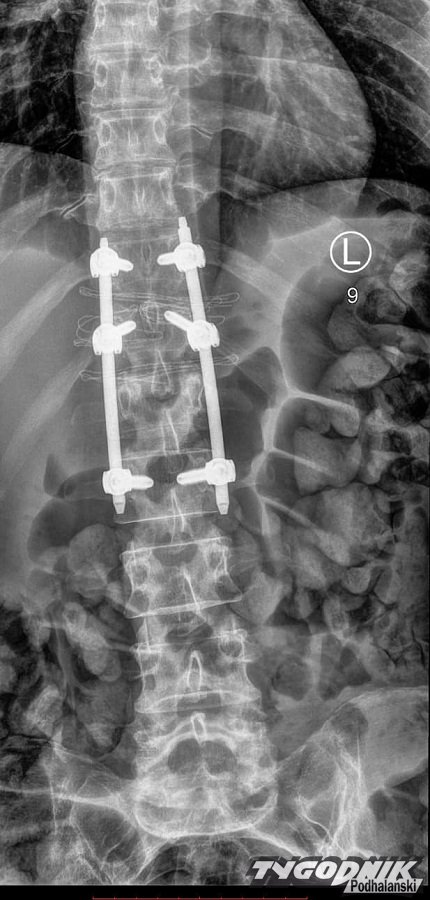

W bezpośredniej konsekwencji zderzenia i pociągnięcia w dół złamałam kręgosłup (niestabilne złamanie, które w każdej chwili mogło doprowadzić do paraliżu) znalazłam się na SORze, a następnie na oddziale ortopedycznym w szpitalu w Nowym Targu. Aktualnie jestem po trwającej cztery godziny operacji stabilizacji kręgosłupa, bogatsza o nowe doświadczenia (m. in. bóle pooperacyjne, jakich nie życzę najgorszym wrogom) i sześć tytanowych śrub stabilizujących złamany krąg L1." - opisuje kobieta na Facebooku.